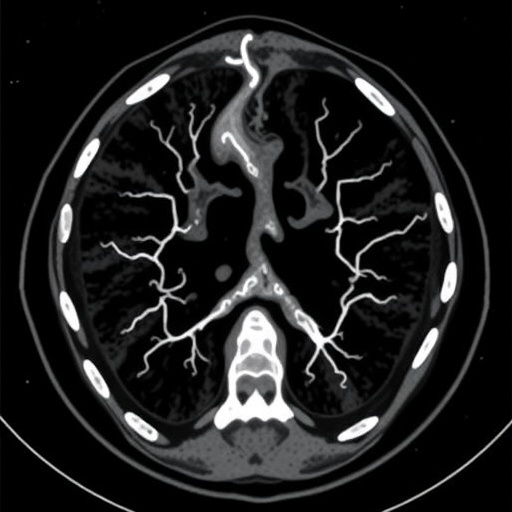

The transparent sample is then examined under an ultramicroscope. A so-called “light sheet”, a thin layer of laser beams, penetrates the tissue. The sample is then analyzed layer by layer, and the computer can then display any section through the tumor, even though it has never been cut up. In this way, insights are gained that were previously impossible: In some tissue samples, for example, milk ducts clogged with cancer cells could be seen.

The new 3D tumor microscopy should make work in pathology much easier. “Instead of inspecting a large number of histological sections under the microscope, pathologists will in future be able to scroll through the images with the mouse, similarly to how radiologists are working today,” says Hans-Ulrich Dodt. The enormous amount of image data that is generated in the process also opens up completely new opportunities in the field of artificial intelligence, believes Dodt: “Perhaps such computer programs could speed up and simplify tumor diagnostics in the future.”